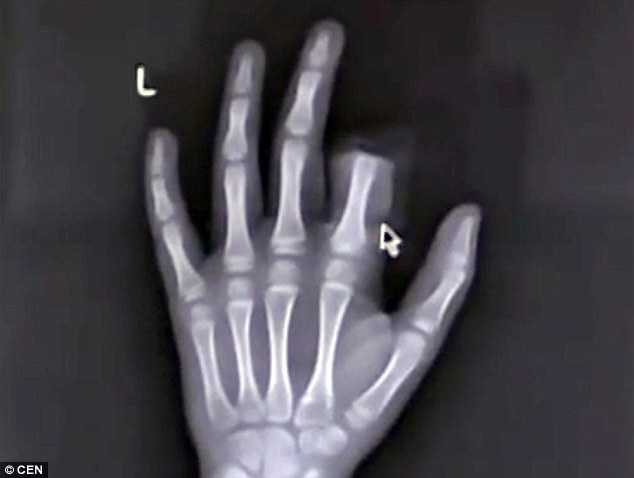

Cậu bé này sau đó đã được bố mẹ đưa vào bệnh viện thành phố với một ngón tay bị cắt lìa.

May mắn thay, do được đưa vào viện kịp thời, các bác sĩ đã tạm thời nối lại đốt tay ngón trỏ bị cắt lìa này sau ba giờ phẫu thuật.

Zhou Rong, một trong những bác sĩ thực hiện ca phẫu thuật cho biết: "Hiện tại các ngón tay đã được kết nối một cách tạm thời. Tuy nhiên, để đảm bảo chắc chắn, chúng tôi cần theo dõi thêm một thời gian”.

Hiện tại Peng vẫn đang rất chật vật với ngón tay của mình bởi nếu cử động quá nhiều sẽ gây ra tình trạng nghẽn mạch dẫn đến việc ngón tay của cậu nguy cơ hoại tử hoàn toàn.